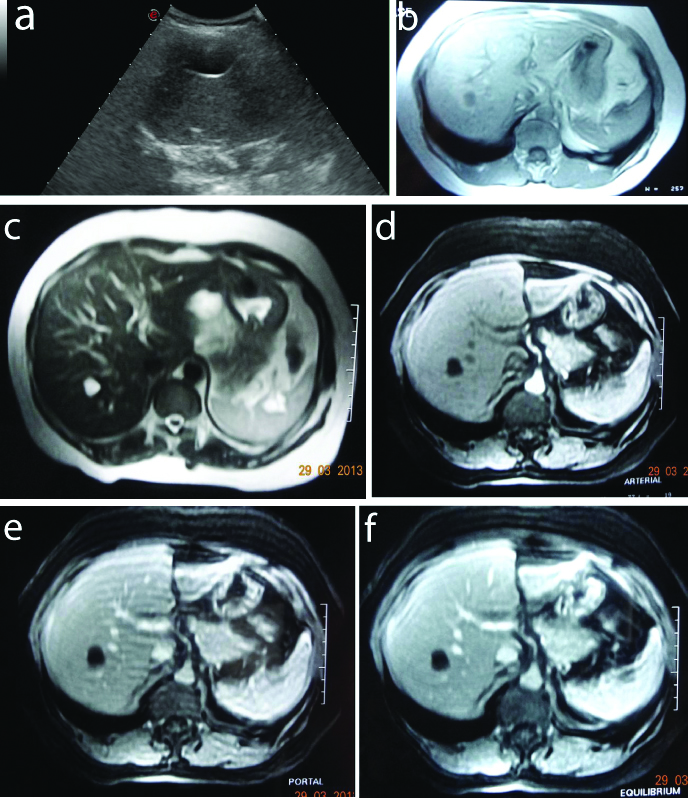

Hepatocellular carcinoma (HCC): This study involved nine patients of Hepatocellular carcinoma and all were seen in males. All the lesions were solitary in nature. Seven lesions were in right lobe, two were in left lobe, all were heterogeneously hypoechoiec on ultrasound and seven lesions (78 %) were hypointense on T1 [Table/Fig-3].

HCC with capsule in a 61-year-old male: a) USG- Hypoechoic hyperechoic rim; b) T1- Hypointense with hyperintense rim (seg IV); c) T2- Hyperintense with isoechoiec rim; d) Arterial- Mild enhancement with capsule; e) Portal- Washout with enhancing capsule; f) Equilibrium- Enhancing capsule.

Two lesions (22%) were heterogeneously hyperintense on T1 due to haemorrhage in the lesions while all the lesions were heterogeneously hyperintense on T2 weighted images.